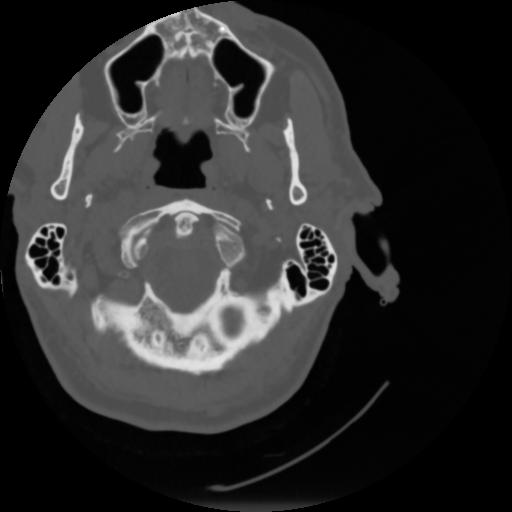

4 CEREBRO,,Vol,0.5,CEREBRO,,